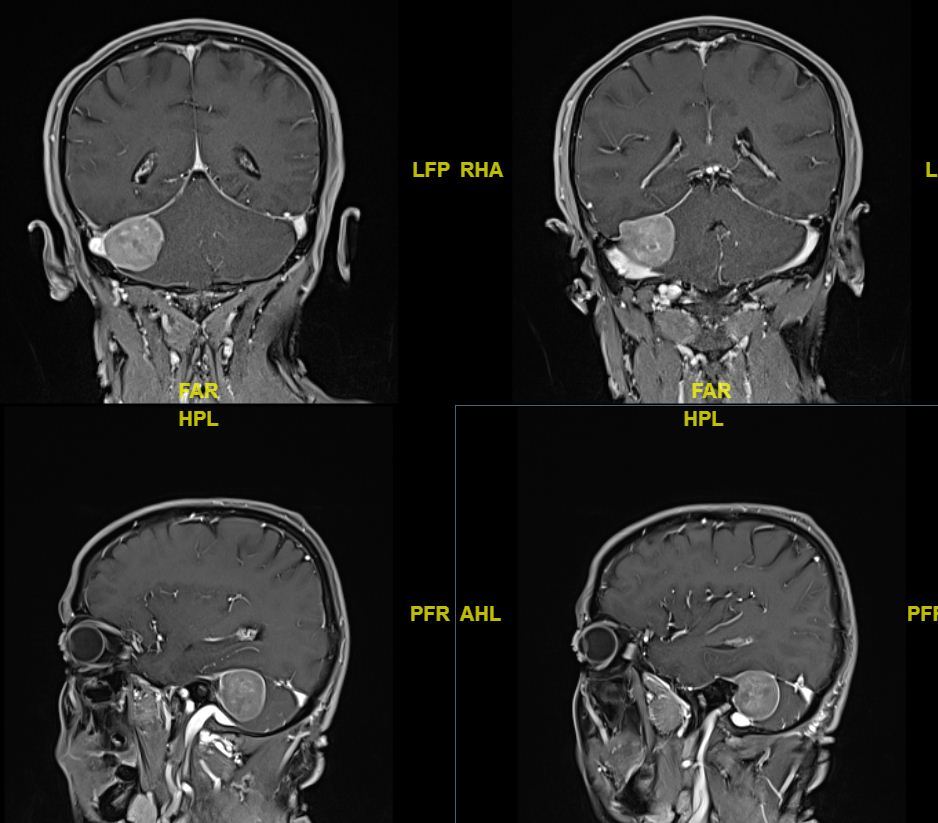

横窦乙状窦交界区天幕脑膜瘤手术病例 - 微医(挂号网)

图片尺寸938x823